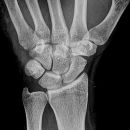

Handgelenk seitlich

Beurteilungskriterien

• Neigung der distalen Radiusgelenkfläche in der Sagittalebene: 10 – 15°

• Kontinuierliche Verlängerungsachse durch Radius, Lunatum, Capitatum und Os metacarpale III. Kontinuität von Handrücken und Unterarmrückfläche (Luxation, nicht-exakte Einstellung? -> Proc.styloideus ulnae im hinteren Radiusdrittel?)

• Scapholunärer Winkel 30 – 60°

• Verstreichen und Ventralverlagerung der volaren Fettstreifen vor dem M.flexor digitorum profundus und M.pronator quadratus

• Grundsätzlich gilt: unklare Verhältnisse -> CT-Indikation